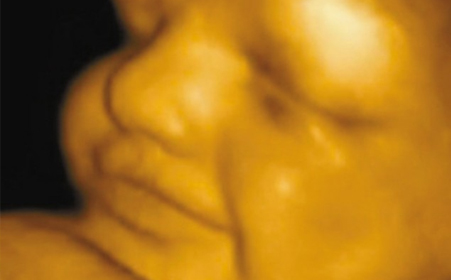

四维彩超主要检查什么?

1、首先四维彩超主要检查 面部畸形:四维彩超检查时重点观察胎儿双眼与眼眶是否等大、等圆,以及眼距测量,硬腭、软腭及上唇弧型曲线是否连续中断等。接下来筛查胎宝宝的颈部,看是否有异常包块。

2、脊柱畸形的筛查是要重点观察脊柱有无隆起,光带有无中断,排列有无紊乱,骶尾部有无肿块等。其他如腹部畸形、肢体畸形等通过逐一观察也不难发觉。

3、其次四维彩超主要检查 神经系统:无脑儿、脑积水、小头畸形、脊柱裂及脑脊膜膨出。在四维彩超胎儿筛畸检查中,首先要筛查的是头颅畸形。

4、检查中,检查者会严谨地观察胎头形态、脑组织(丘脑、小脑、小脑蚓部、颅后窝池、侧脑室)以及中线距两侧颅骨板的距离等,筛查无脑儿、露脑、脑积水等情况。